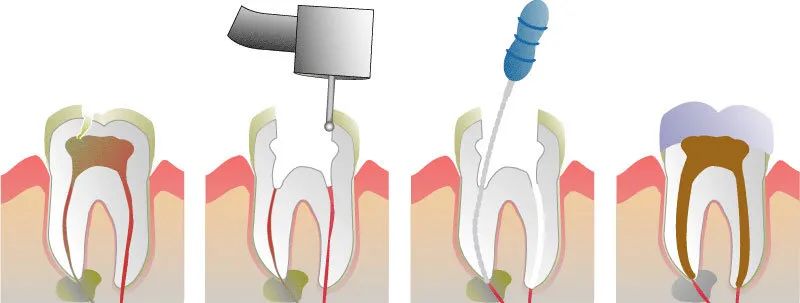

根管治疗的过程

不可恢复的牙髓最终都会走向坏死的结局,所以根管治疗需要清除这些牙髓,并将掏空的根管密封填满,以避免根管内以及根尖周围的组织未来继续受到感染。

根管治疗会涉及以下步骤:

1.测量根管长度。通过X光、根管长度测量仪等工具确定根管的准确长度,以保证清洁时可以触及牙根内全部区域,达到最佳的清洁效果。

2.使用专用工具清洁根管。清洁过程会使用根管锉配合根管冲洗液(如次氯酸钠)来清理根管,去除细菌、黏在根管壁上的软组织甚至钙化的根管壁。下面的视频演示了根管清洁的过程。

3.使用根充材料将根管密封填充。当用根管锉将根管内部清洁干净后,牙医会用不可吸收、并且在X光上会显影的材料将根管填满封死。

根管填充